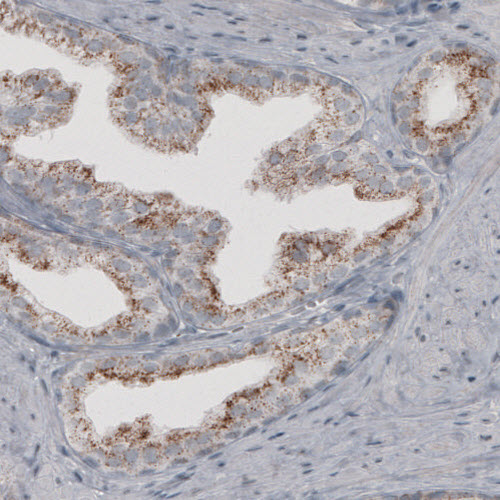

Immunohistochemical staining of human kidney shows granular cytoplasmic immunoreactivity in renal tubules.